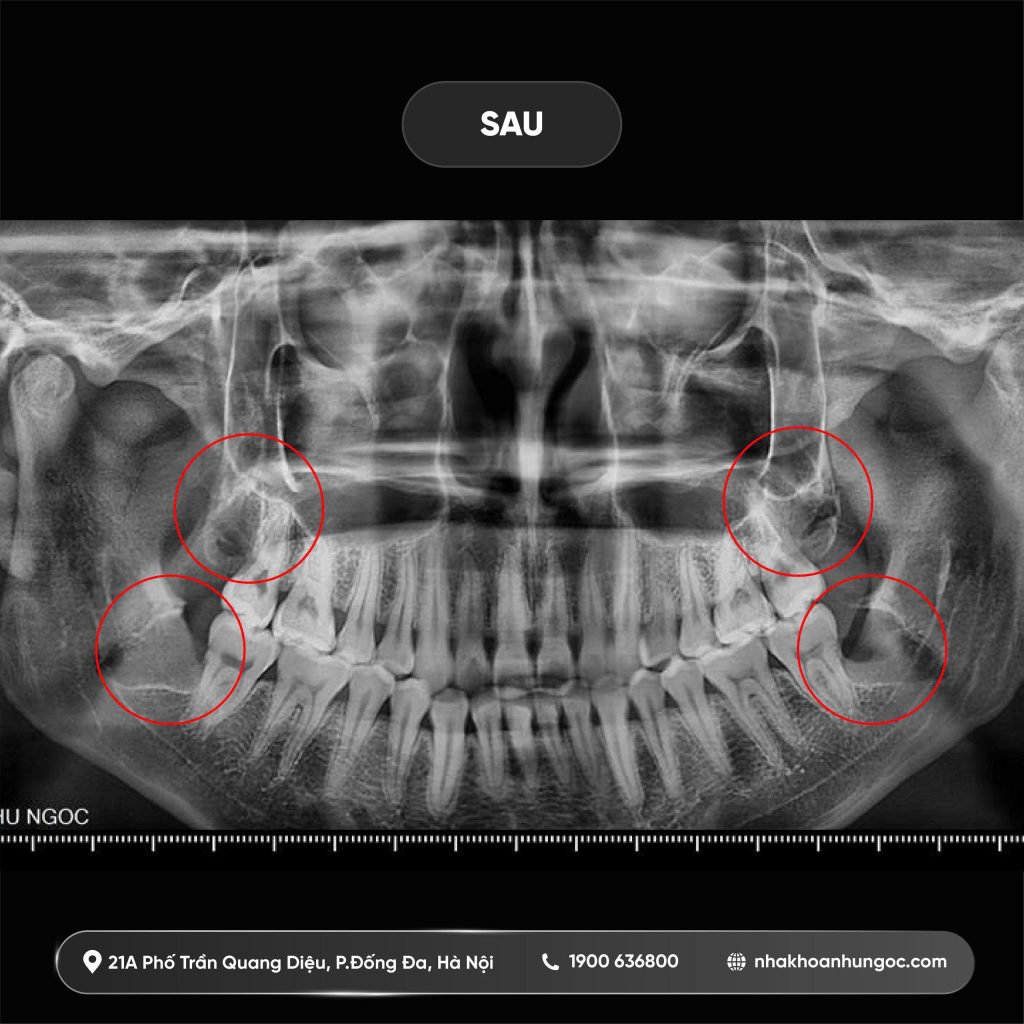

Sau khi tiến hành chụp X-quang toàn hàm (Panorama) và được các bác sĩ chuyên khoa thăm khám kỹ lưỡng, nguyên nhân gây ra những cơn đau dai dẳng của Linh đã được xác định rõ ràng. Không chỉ một, mà cả 4 chiếc răng khôn của Linh đều gặp vấn đề nghiêm trọng:

2 răng khôn hàm dưới mọc ngang: Đâm thẳng vào chân răng số 7 (răng nhai chức năng quan trọng nhất). Tình trạng này nếu kéo dài sẽ gây hỏng răng số 7, dẫn đến nguy cơ mất răng vĩnh viễn.

2 răng khôn hàm trên mọc chìa: Hướng mọc lệch đâm trực tiếp vào niêm mạc má, gây cọ xát, nhiệt miệng và tạo cảm giác đau rát mỗi khi cử động cơ hàm.

Với tình trạng mọc lệch và mọc ngầm phức tạp này, việc trì hoãn sẽ chỉ khiến tình trạng viêm nhiễm nặng hơn.

Hình ảnh Quý khách hàng sau điều trị tại nha khoa Như Ngọc